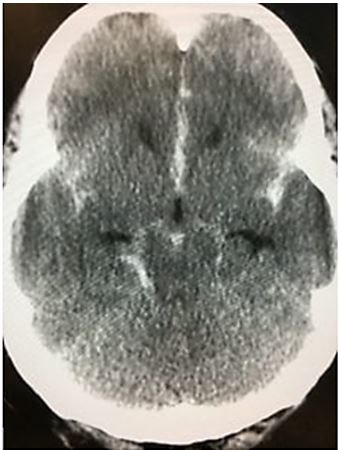

Imaging. Results of head CT, below.

Subarachnoid Hemorrhage from the Emergency Medicine 1-Minute Consult Pocketbook